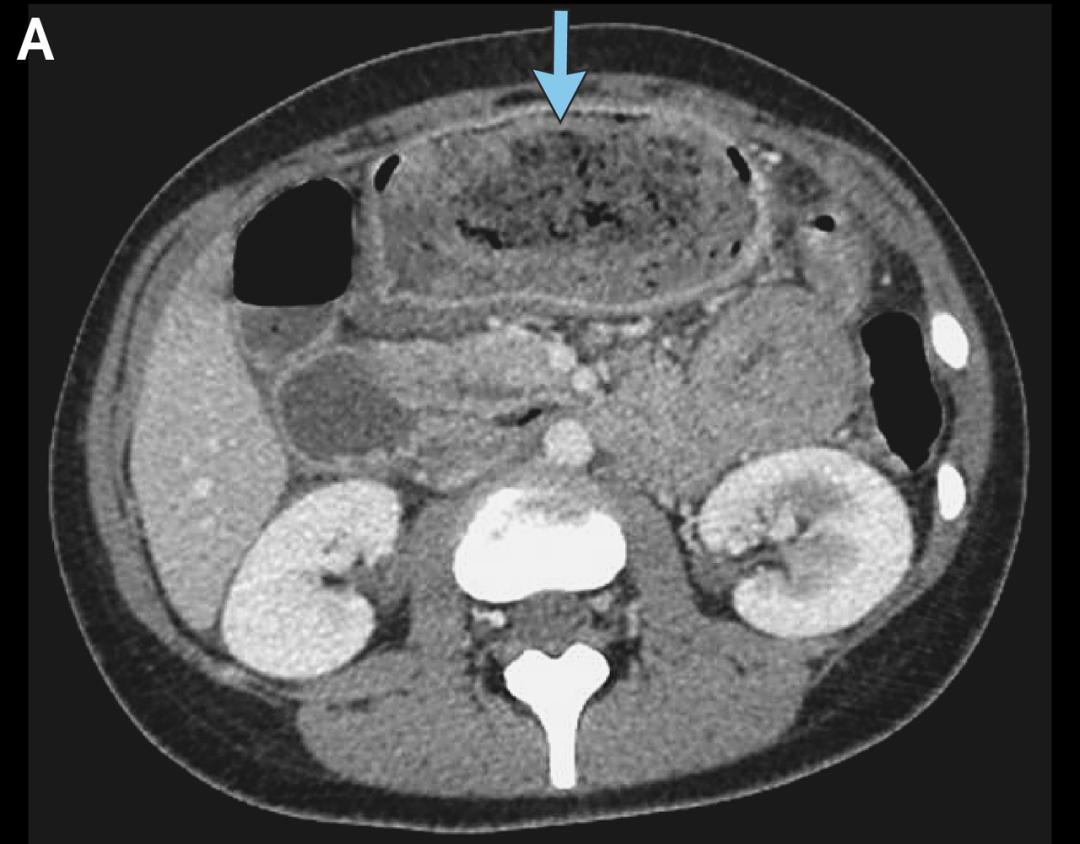

左滑查看更多图片:胃石示意图、手术中看到的毛发性胃石、CT检查中的胃石 | 参考文献[1]

医生一一排查,把她腹痛、恶心呕吐的最可能原因集中到了两种疾病上。一种是消化性溃疡,因为患者近一周为缓解腰背痛吃了24片布洛芬。另一种是胃石,因为患者的长期用药中有两种会增加胃石形成的风险。

接下来的胃镜检查给出了答案,医生在她的胃里看到了一大块胃石,诊断胃石症。